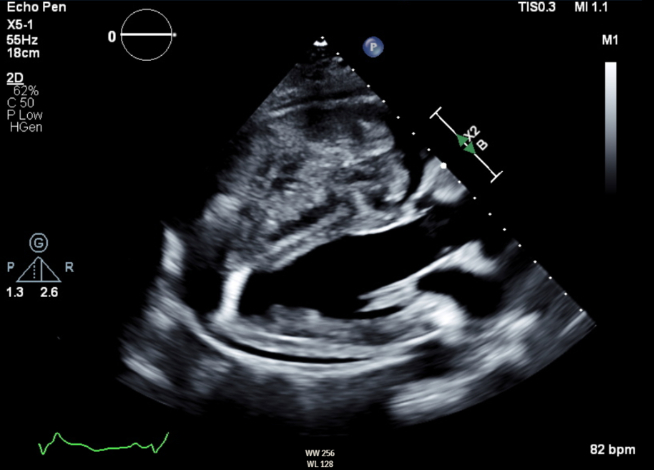

Cardiac MRI confirmed a large mass occupying a significant majority of the right ventricular cavity with central necrosis (Figure 2). Cardiac surgery deferred surgical resection given the significant invasiveness of the mass and the inability to obtain negative margins without causing substantial myocardial injury. Transcatheter biopsy was pursued with pathology revealing metastatic sarcoma.